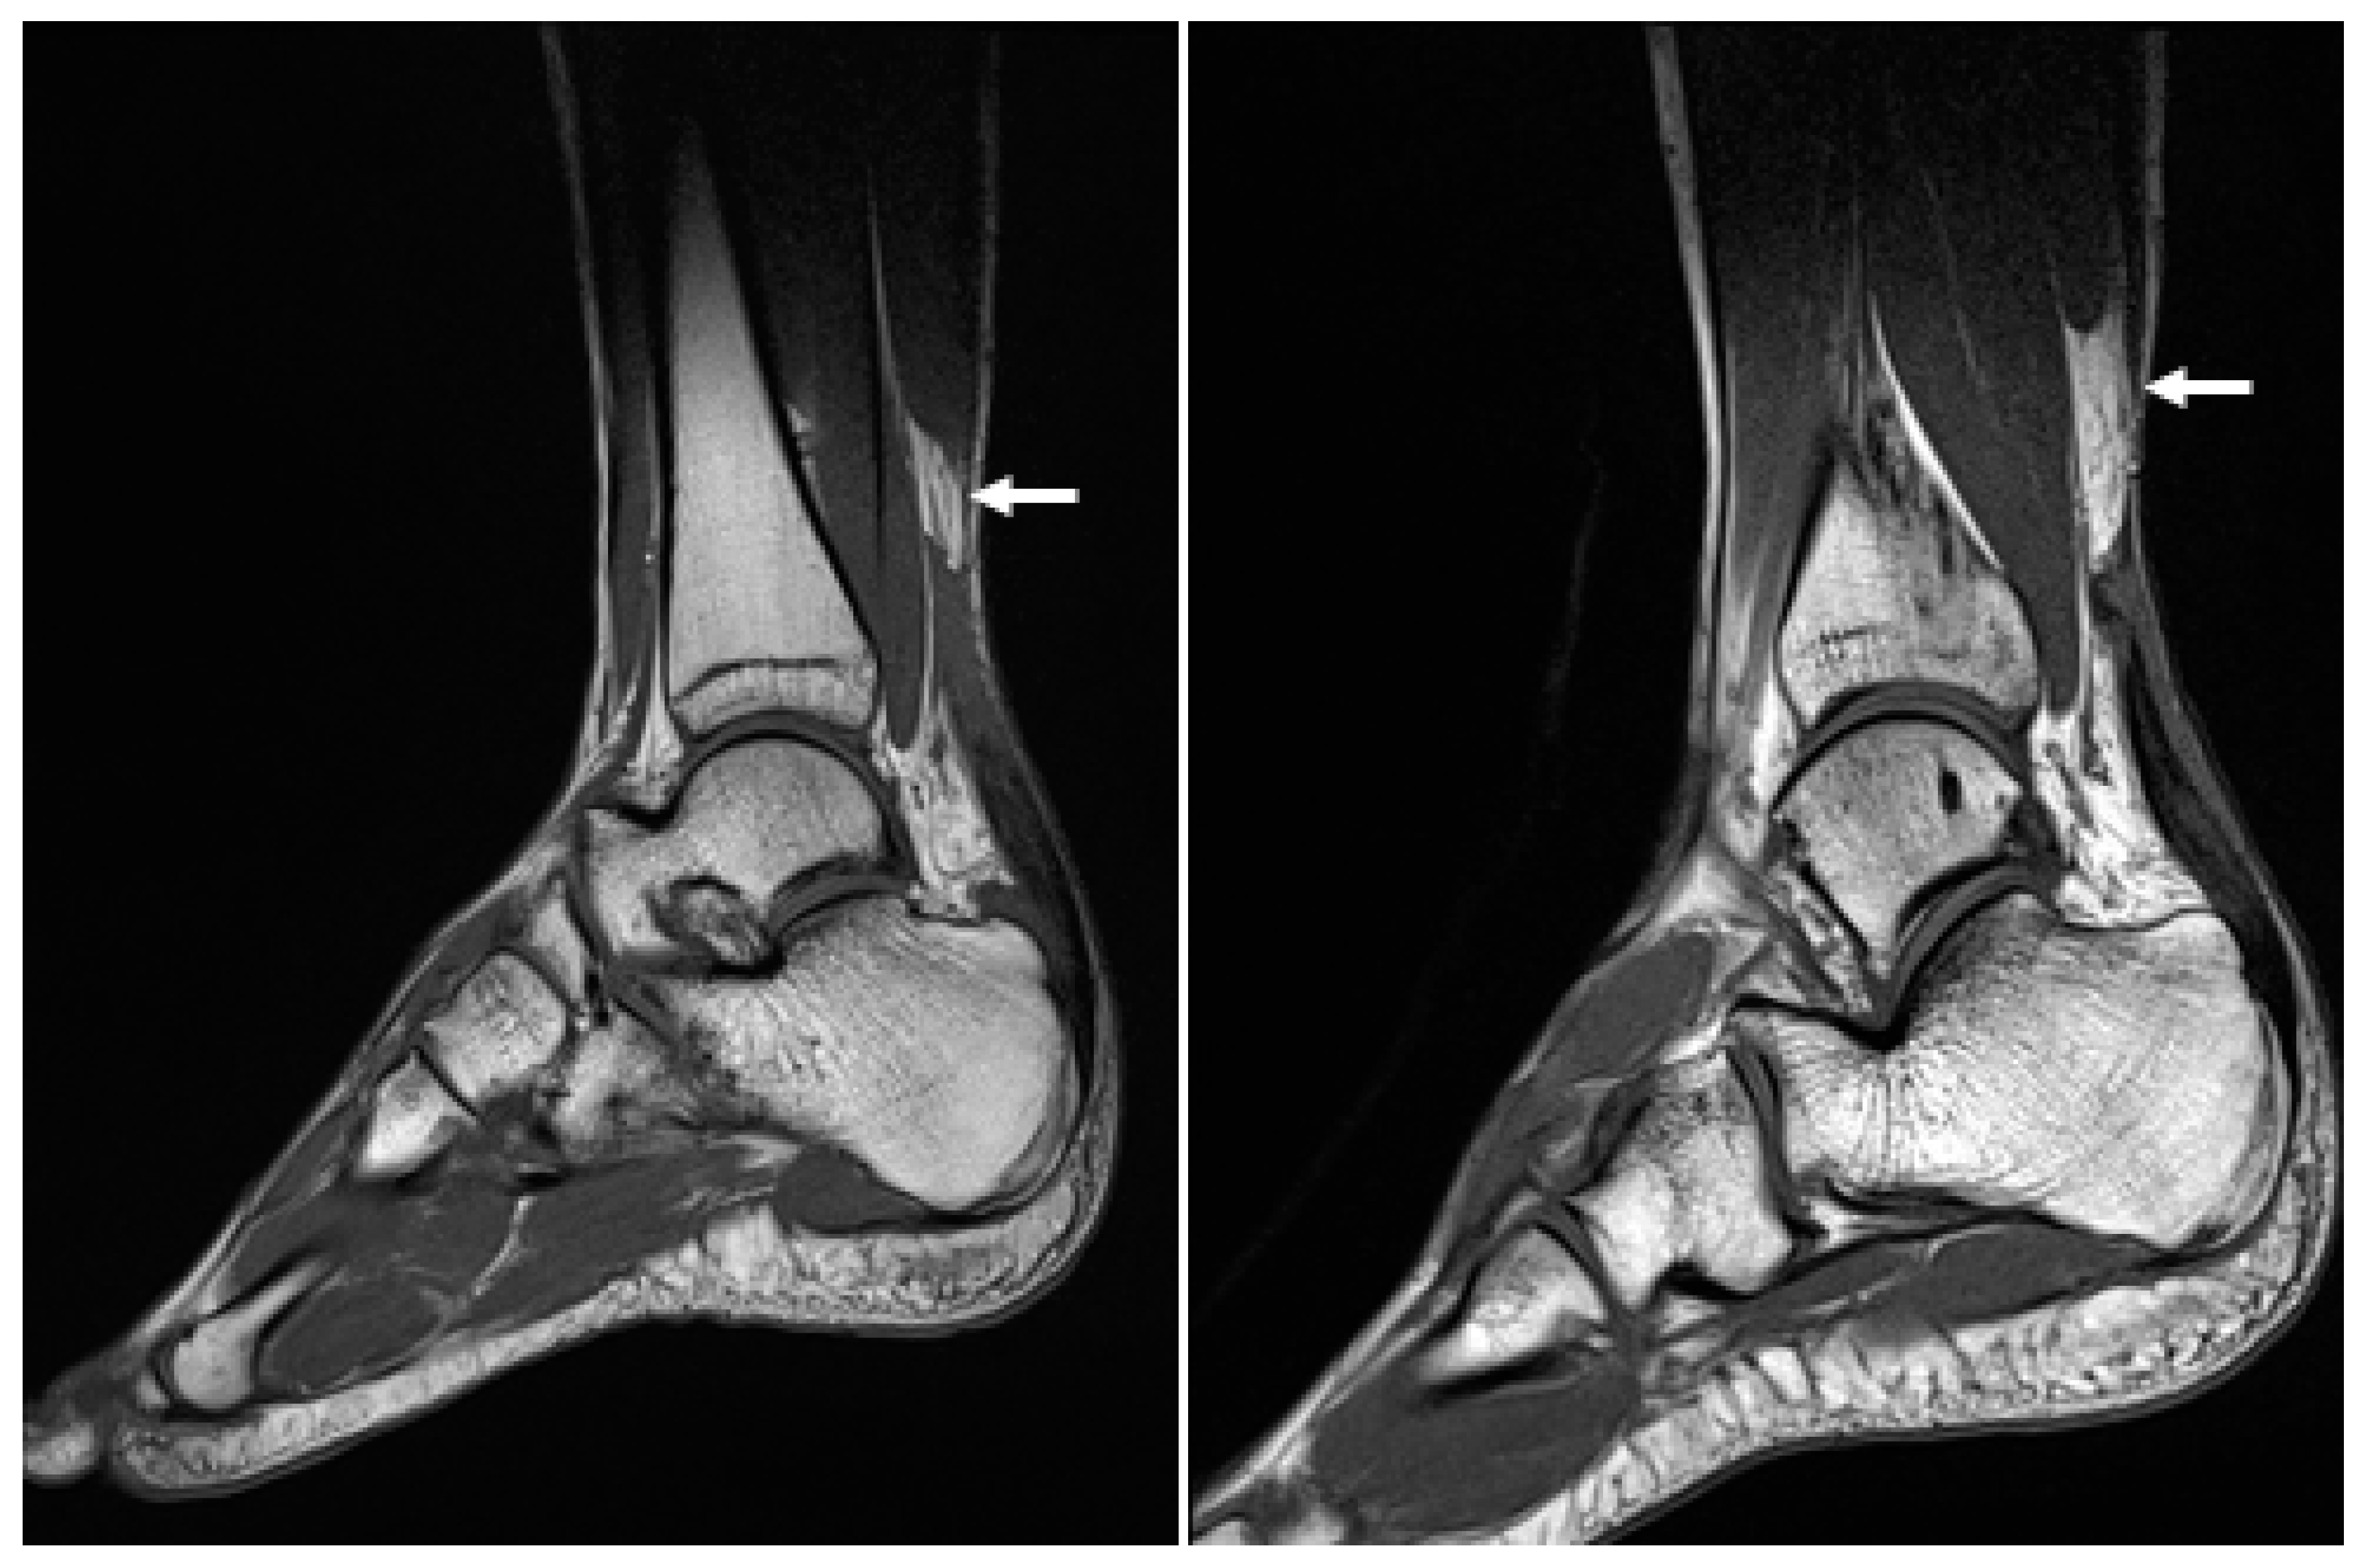

Figure 7. Postoperative (19 months after operation) sagittal magnetic resonance images of both ankles showing good continuity of the Achilles tendons.

2.3. Postoperative Care